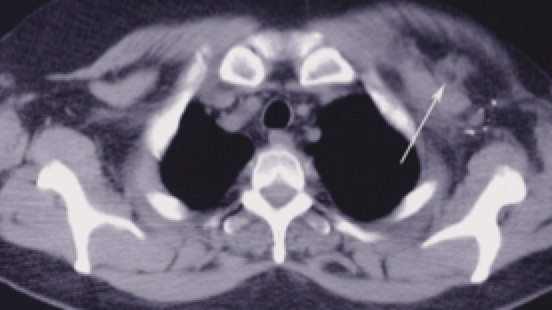

Fields and treatment volumes

CT simulation is very useful to precisely delineate the target volumes. The IMN vessels are found within the first 3 intercostal spaces and are the region where the IM nodes are at highest risk. Using the IM vessels. The depth of the Level III axillary and supraclavicular nodes is also variable. The depth can be easily determined from CT imaging. Contouring these nodes in the treatment planning system can insure they are adequately treated. Studies of treatment planned patients using a 6 MV anterior oblique supraclavicular field prescribed to a depth of 3 cm can significantly underdose nodes in patients who are overweight or obese.